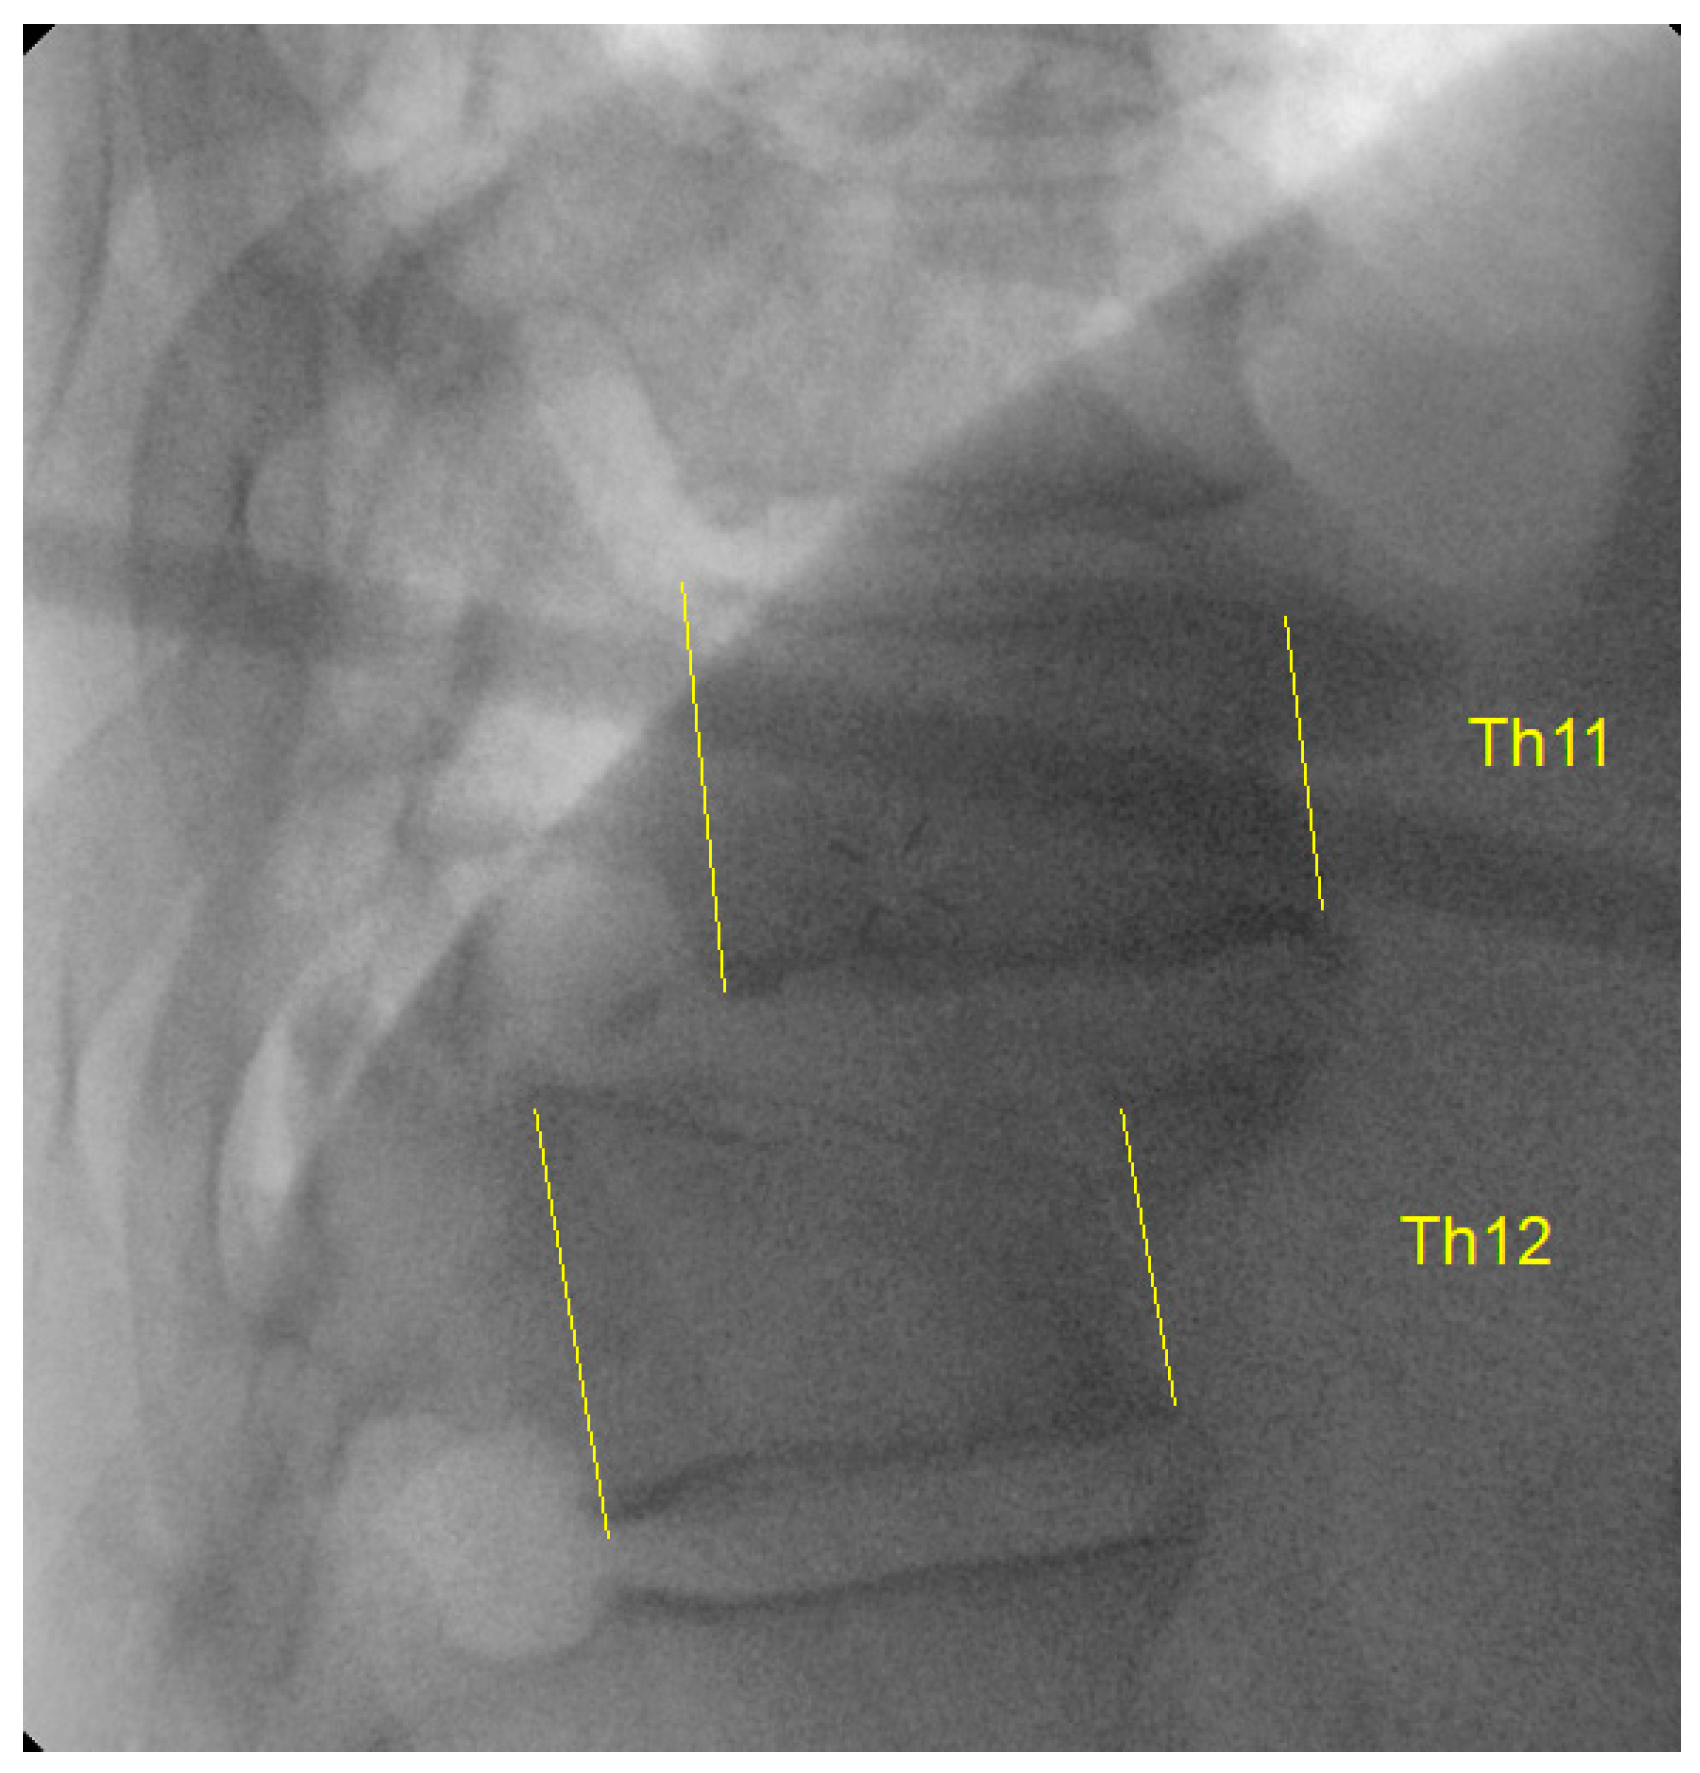

Figure 3.

Intraoperative fluoroscopic image showing dislocated Th11–Th12 levels. Yellow lines represent the anterior and posterior vertebral body height along with the translation noted between the vertebral levels that resulted in the facet dislcoation.